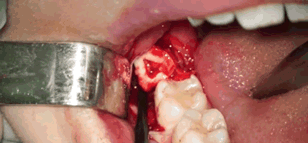

前

方

高

能